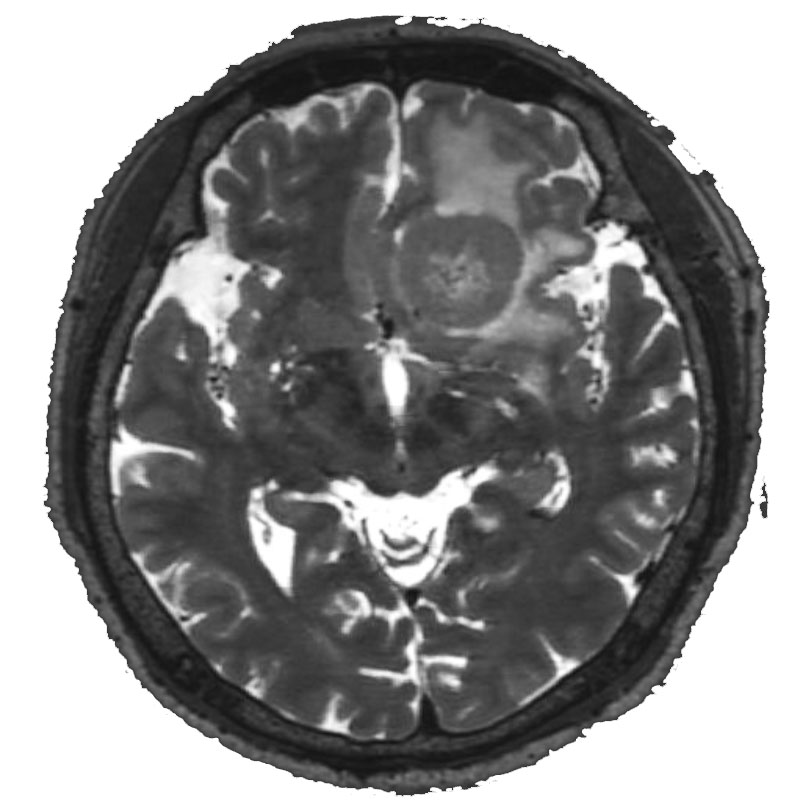

脳室内腫瘍

摘出術

北野/濵田